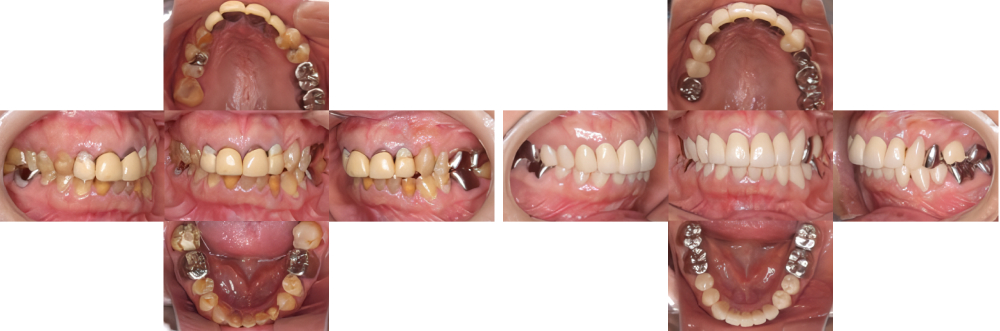

全顎保険治療

術前

術後

| 治療内容 | 全顎的に保険内で治療を行った |

|---|---|

| 治療期間・回数 | 約2.5年・約50回 |

| 費用 | 保険適用となります |

| リスク・副作用 |

| 治療内容 | 全顎的に咬合再構成を行い保険内で治療を行った |

| 治療期間・回数 | 約4年・約50回 |